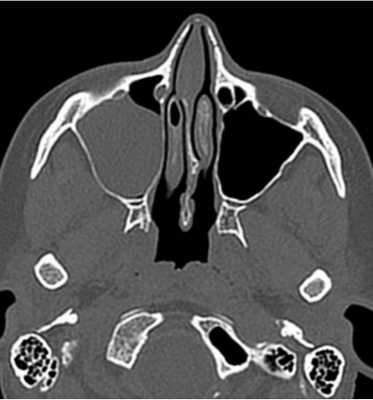

Слева — КТ-снимок одонтогенной кисты в верхнечелюстном синусе, справа — МР-фото образования (указано стрелкой) в гайморовой пазухе

КТ (справа) и МРТ (слева) носовых пазух в коронарной проекции - фото